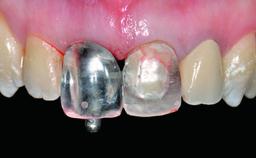

Replacement of a Perforated Upper Left Central Incisor: Early Placement of an RC Bone Level Implant

A 28-year-old patient presented at her general dentist’s office and complained about the appearance of her tooth 21. The patient had a history of trauma to this tooth. Endodontic treatment had been performed in the past and a crown placed on the tooth. A procedure to replace the old crown was performed by her dentist; however, a perforation on the middle third of the root occurred, and extraction of tooth 21 was suggested. Upon clinical and radiographic examination of the patient, who had been referred to us, replacement of tooth 21 by a dental implant appeared to be indicated.

Bone Augmentation Horizontal|Simultaneous

Abutment Type Customized